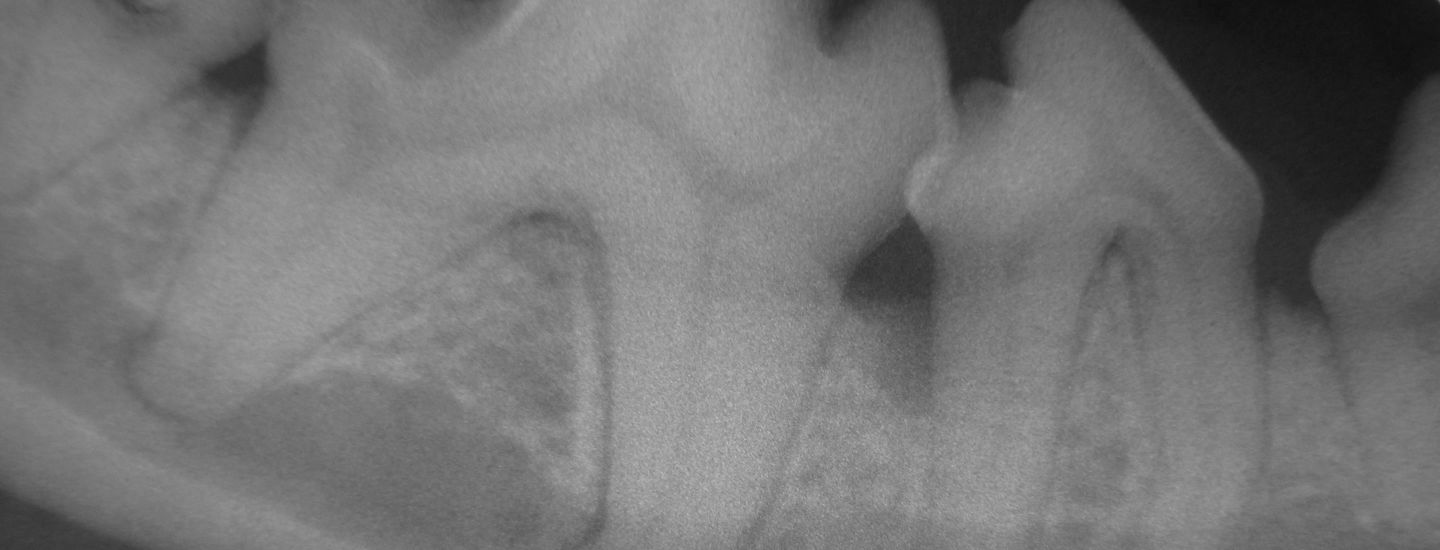

A radiografia intra-oral é uma importante ferramenta de diagnóstico por imagem utilizada na Odontologia Veterinária, pois com ela, é possível avaliar com detalhes as lesões radiculares ou ósseas de cada elemento dentário, evitando a sobreposição de imagens.

É tão importante que “não há tratamento dentário realizado por um bom dentista veterinário sem avaliação radiográfica”, principalmente em gatos, portadores de lesão de reabsorção dentária.

Com o Rx intra-oral, é possível se diagnosticar as mais diversas lesões em cães, gatos, roedores e coelhos. Veja alguns exemplos: